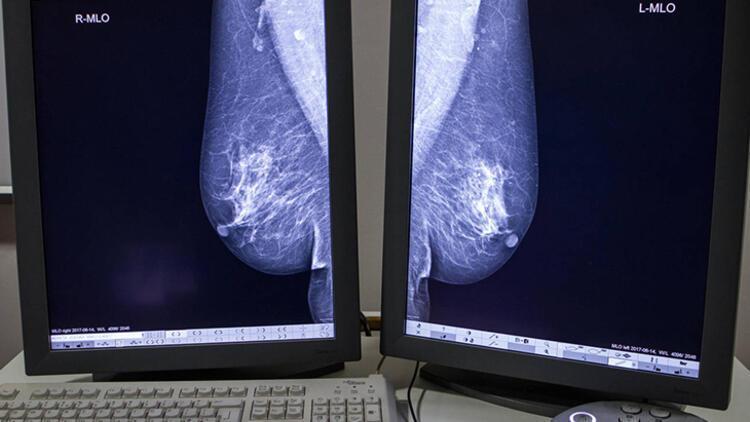

Prof.Dr. Sıtkı Gürkan Yetkin, meme kitlesi şikayeti ile başvuran hastada meme ve koltukaltı bölgesinin muayenesi yapılması gerektiğini vurgulayarak, "Kitlenin tanısı için öncelikle yapılması gereken görüntüleme tetkikleri mamografi ve ultrasonografidir. Hangi tetkikin öncelikle yapılacağı hastanın yaşına göre değişiklik gösterir.

35 yaş üzerinde mamografi yapılması önerilirken 35 yaş altında meme dokusunun dens olması ve mamografinin duyarlığı düşük olduğundan ilk tercih edilecek yöntem ultrasonografi olmalı.

Bu tetkiklerle tanı konulamaz ise manyetik rezonans görüntüleme (MR) ileri tetkik olarak uygulanmalı. Görüntülemeler sonucunda öngörülen tanı, görüntüleme eşliğinde yapılan kalın iğne biyopsisi ile kesinleştirilir. Konulan kesin tanıya göre tedavi planlanır" dedi.